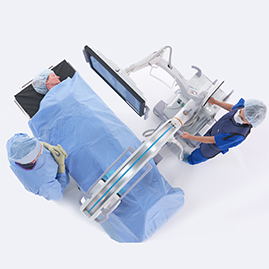

All in ONE for tight small & busy OR

In operating rooms, which are generally very confined and busy spaces, a thin system does not take up too much

space <1,40m2 compact foot print.